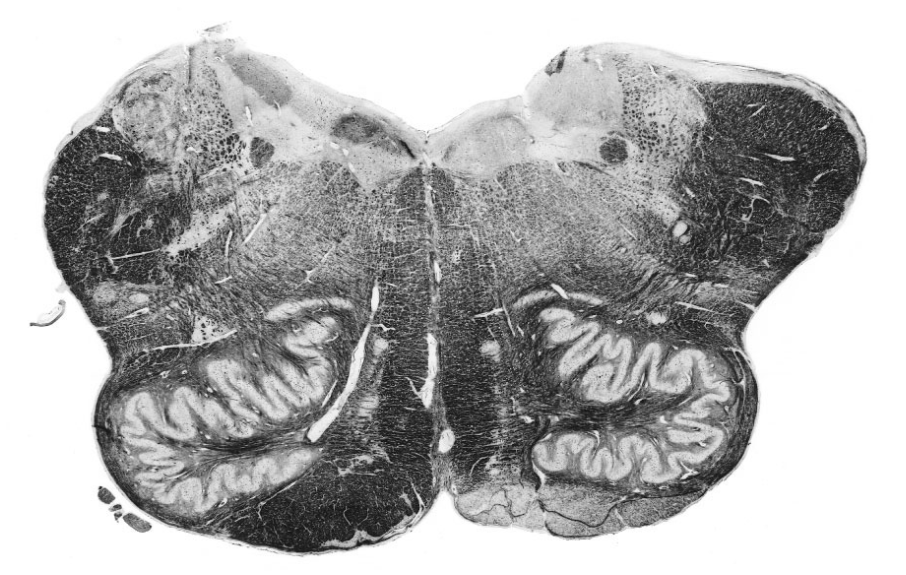

The following section of the brainstem is typical of which level?

rostral medulla